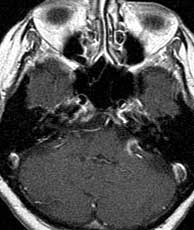

T1 pre-gad T2 MRA

Diagnosis: Aneurysm of the left cavernous internal carotid artery.

Cavernous sinus ICA aneurysms are more common in women and typically present over the age of 50. They may cause palsies of cranial nerves 3, 4, 6, as well as the first and second divisions of the trigeminal nerve since these nerves lie within the cavernous sinus. A variable amount of thrombosis may be present. In this case, the aneurysm is most likely partially thrombosed due to the complex, layered signal. The presence of the phase encoding artifact proves that there is at least some flow. Related Cases